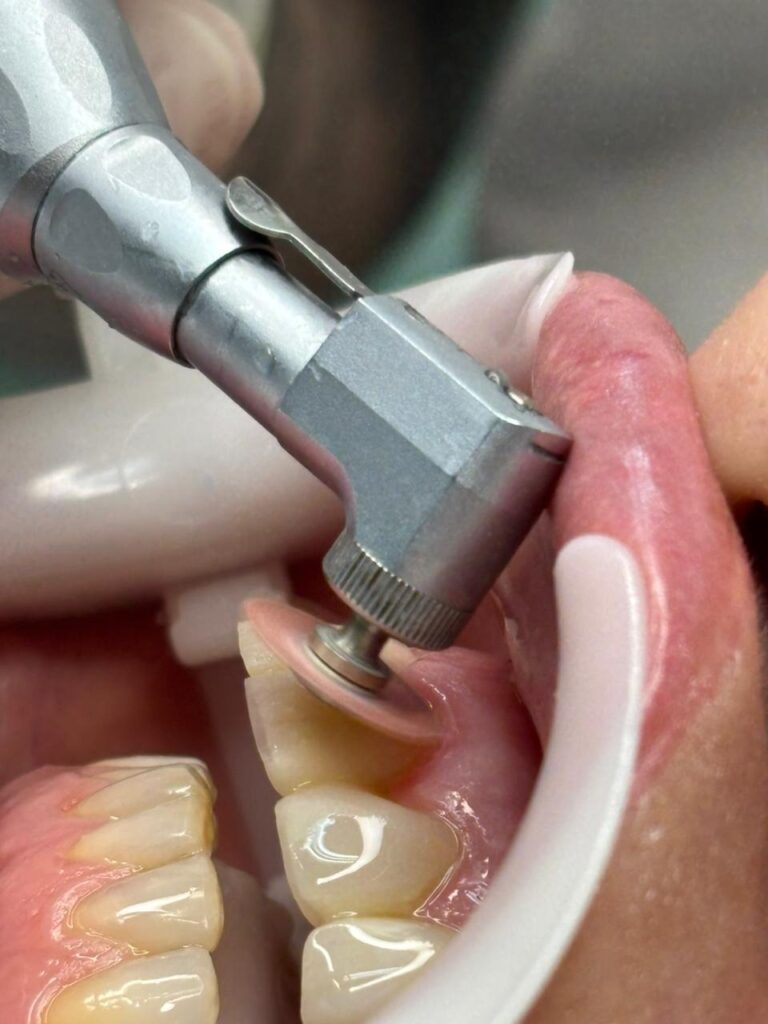

Figura 8: Aspecto final sem acabamento.

Após a escultura final, foi realizada a remoção do isolamento, checagem da guia canina, términos cervicais e ponto de contato, seguido do acabamento e polimento utilizando a baixa rotação com discos de lixa (TDV) com água. Dando sequência, utilizou-se pontas espirais JIFFY POLISHER (ULTRADENT), e por fim pontas Enhance, também em baixa rotação com pedra pomes e água, respeitando as áreas de sombra e espelho, etapas essenciais para o sucesso clínico e a longevidade das restaurações. O polimento adequado potencializou o brilho superficial, reduziu a adesão de biofilme e conferiu um aspecto natural à faceta, integrando estética ao conjunto dentário, conforme apresentados nas figuras 9 e 10.

Figura 9: Acabamento com disco de lixa.

Figura 10: Polimento com espiral abrasiva média.